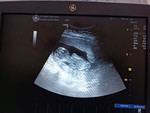

Saya praggy 6week.... Tadi scan... Ade nampak cyst saiz 4cm... Saya terus down...

Bahaya tak cyst semasa praggy??